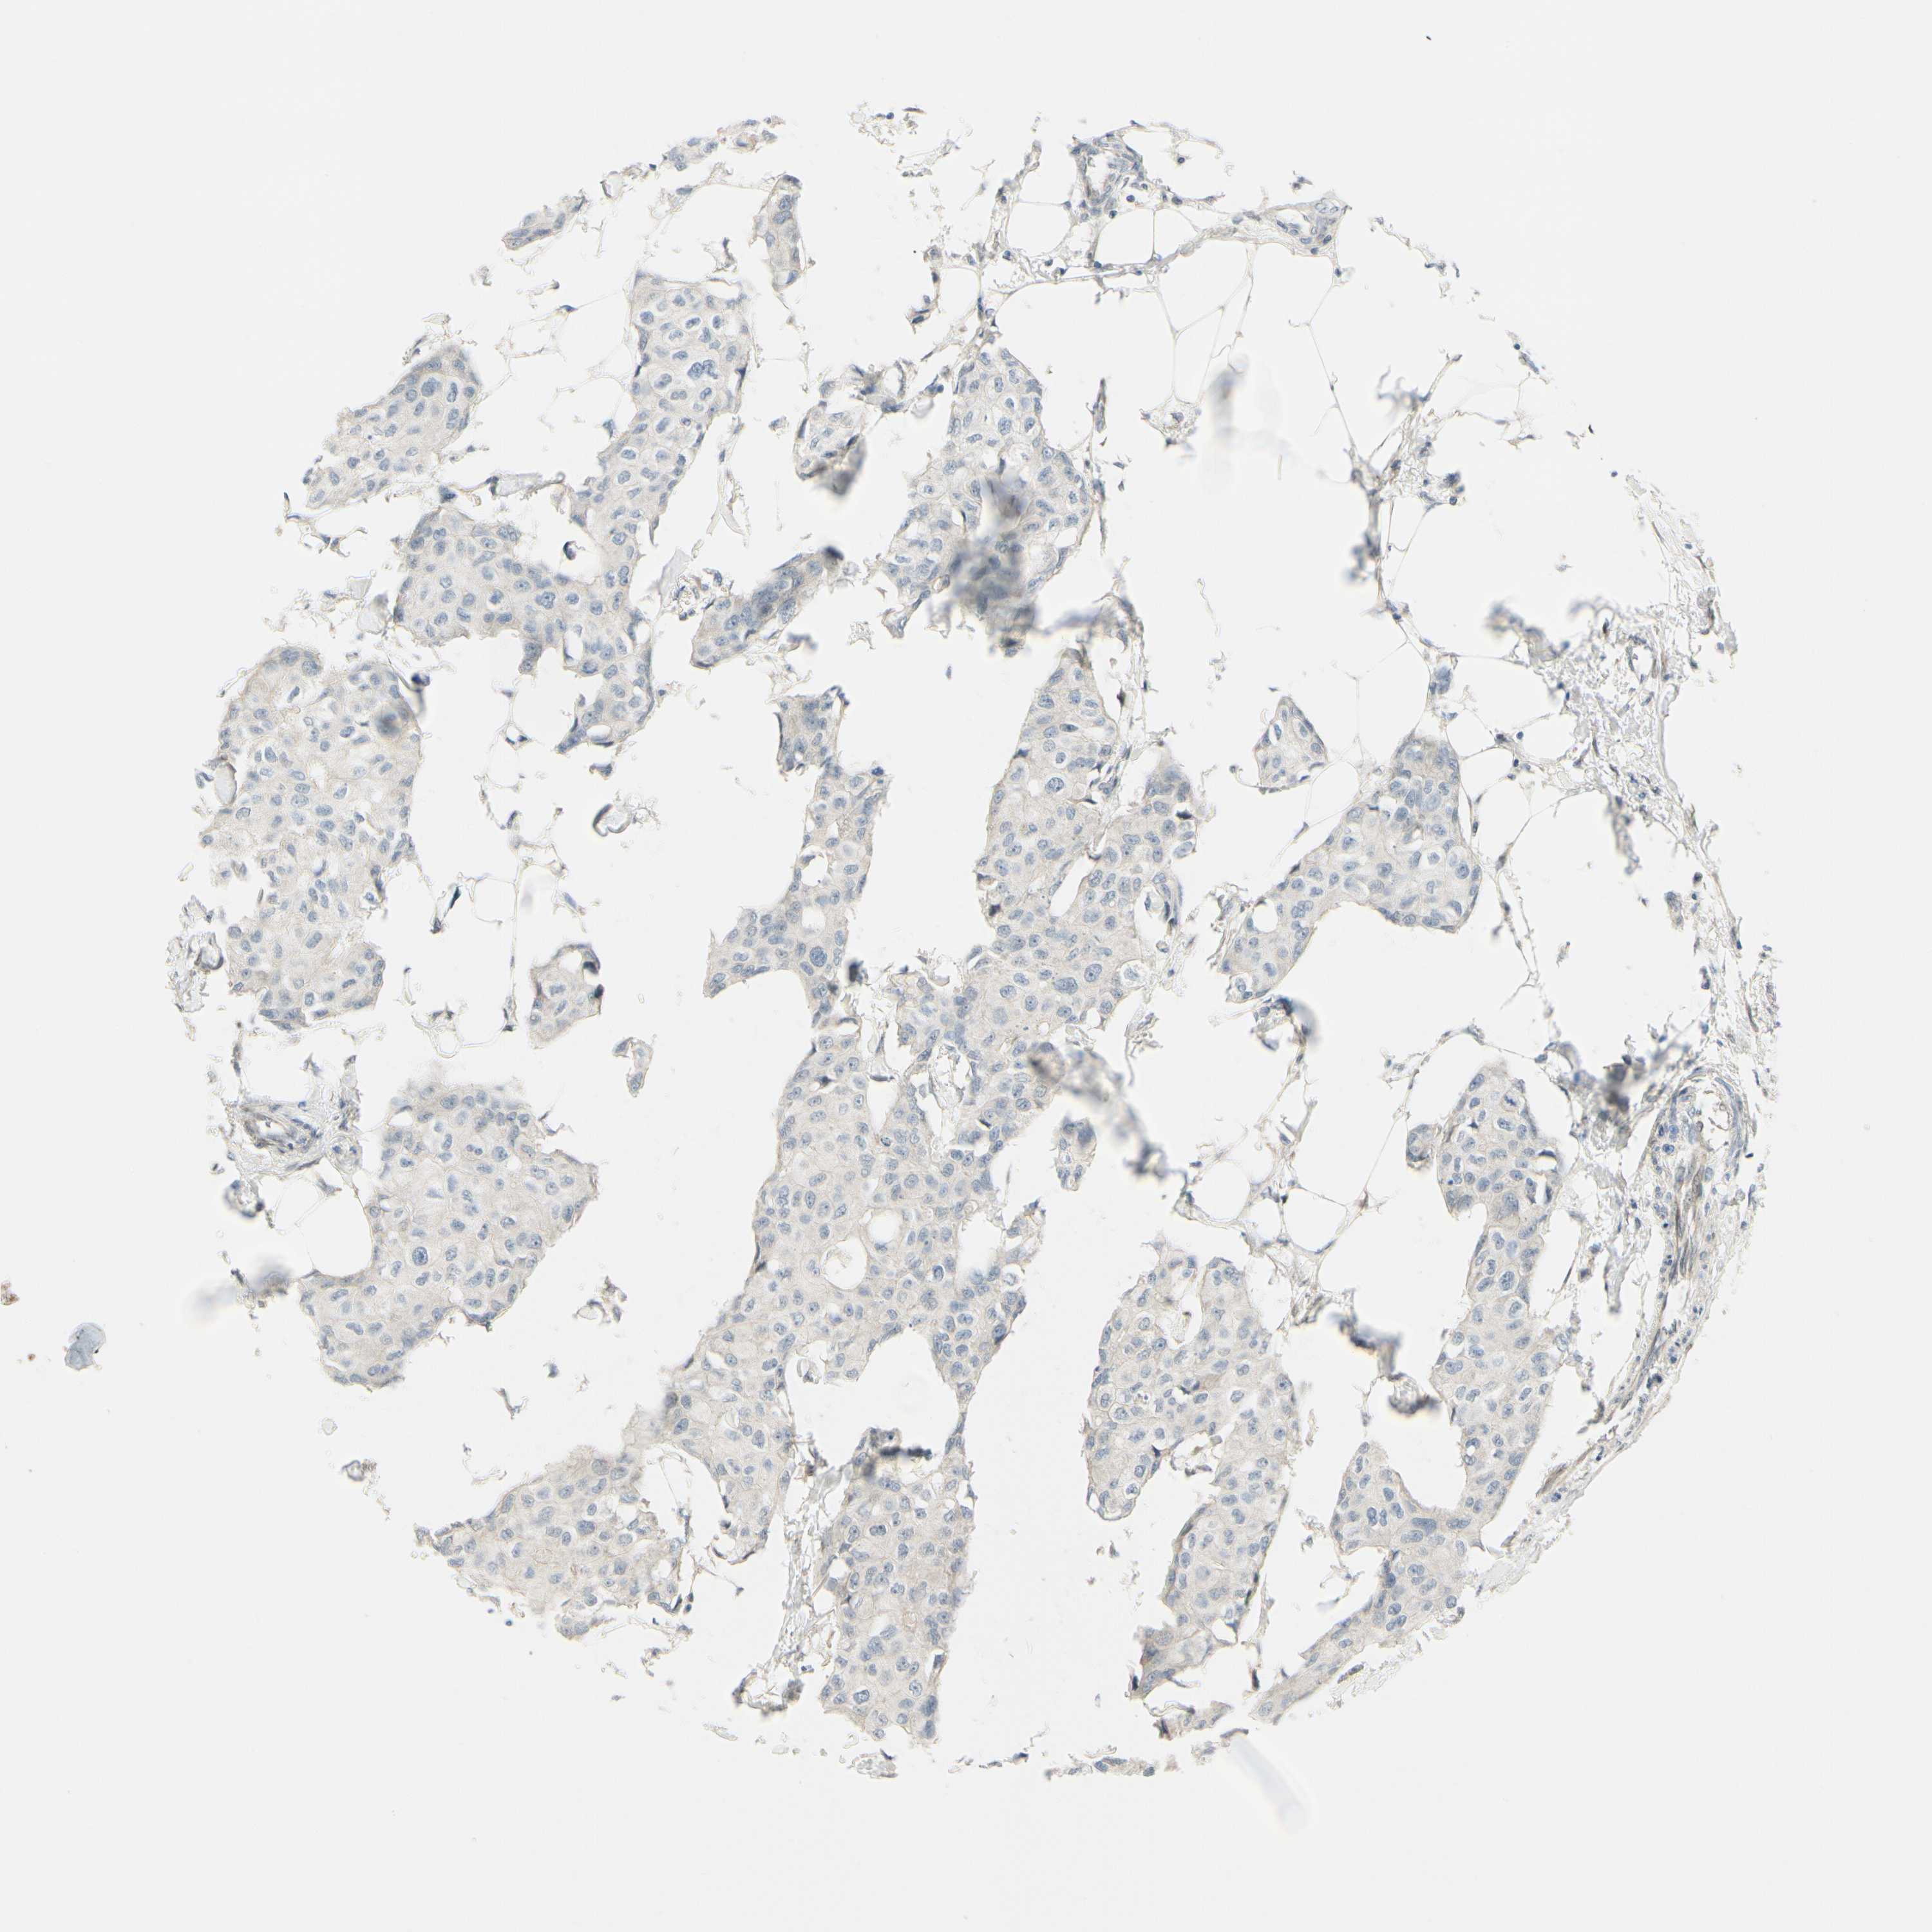

CANCER BREAST CANCER Show tissue menu

BRCA TCGA BRCA VALIDATION PROTEIN EXPRESSION